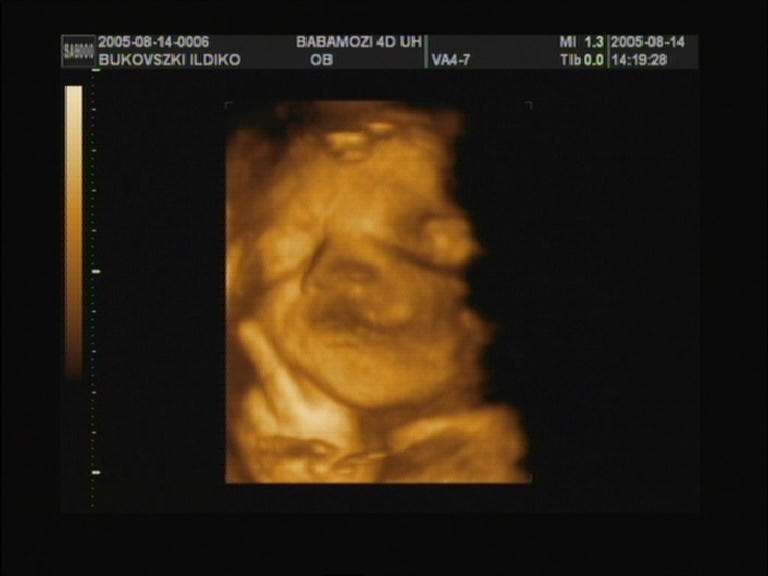

már most bemutat a kis

ujjacskájával!!!!! (nem tudom ki mit lát-nemlát a képben, mindenesetre bal alsó sarokban van a keze kinyújtott ujjal) |

"hagyjatok már békén!!" |